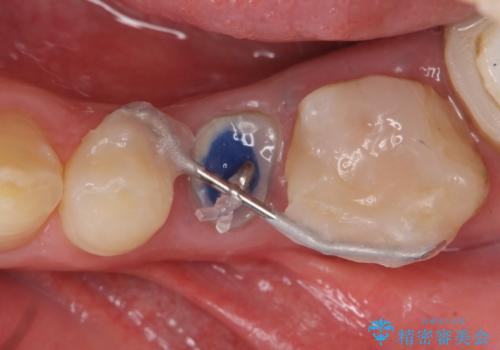

痛みの原因は6番目の虫歯であること、5番目、6番目の歯は歯茎より深い虫歯であり現状では保存が難しいことを説明した上で、歯を挺出させる部分矯正と歯茎を下げる歯周外科を行いました。

手術後歯茎の治癒を待ち、オールセラミッククラウンによる補綴を行いました。